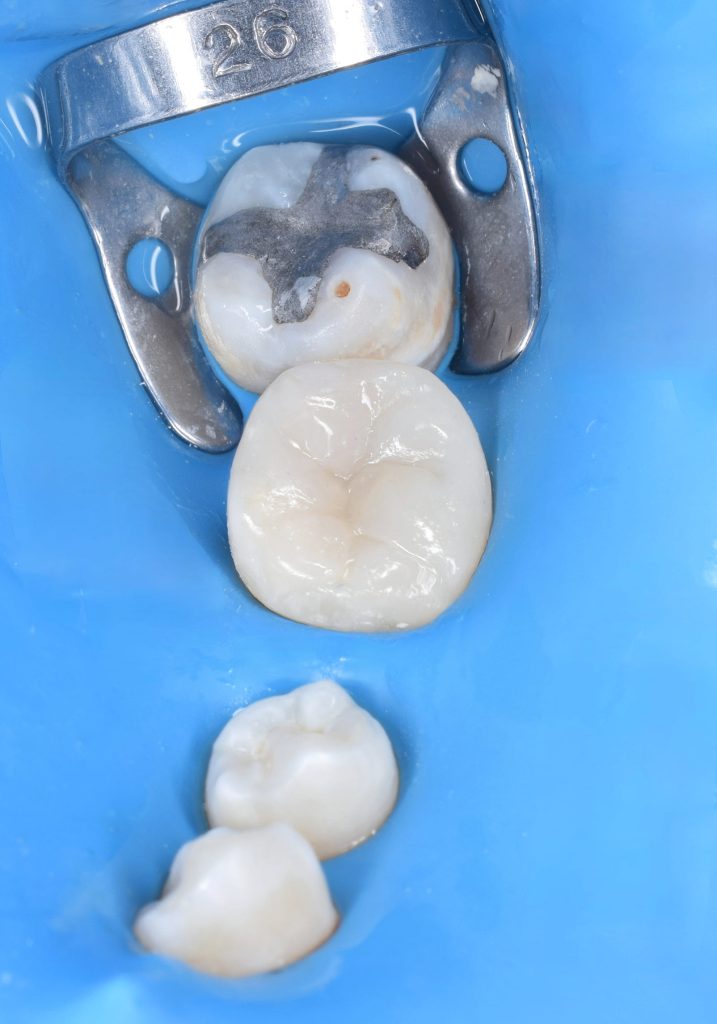

Multiple isolation

Direct view for isolation

B4 in action